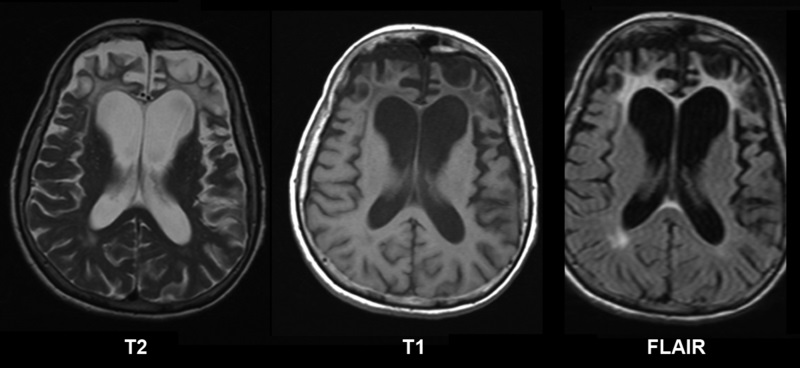

Uno de los casos más comunes de atrofia cerebral es la que se caracteriza por acercamiento entre las superficies corticales y epindimarias, ensanchamiento de los surcos cerebrales, y adelgazamiento de las circunvoluciones de los lóbulos frontales.

De hecho, el envejecimiento implica una reducción progresiva de las conexiones y de las estructuras cerebrales. Para poder distinguir una atrofia patológica de una atrofia benigna asociada a la edad resulta importante llevar a cabo una adecuada exploración neuropsicológica que especifique las características del deterioro cognitivo.

La esclerosis múltiple es una enfermedad que se caracteriza por la aparición de lesiones desmielinizantes, neurodegenerativas y crónicas en el sistema nervioso central.

Esta patología suele provocar una disfunción de la barrera hematoencefálica (sistema de vasos capilares que protege la entrada de sustancias en el cerebro a través de la sangre).

De este modo, macrófagos y linfocitos pueden cruzar la barrera hematoencefálica de los sujetos con esclerosis múltiple y acceder al cerebro, originando daños cerebrales y provocando síntomas como hormigueo, debilidad, falta de coordinación, rigidez muscular, trastornos del habla o alteraciones visuales.